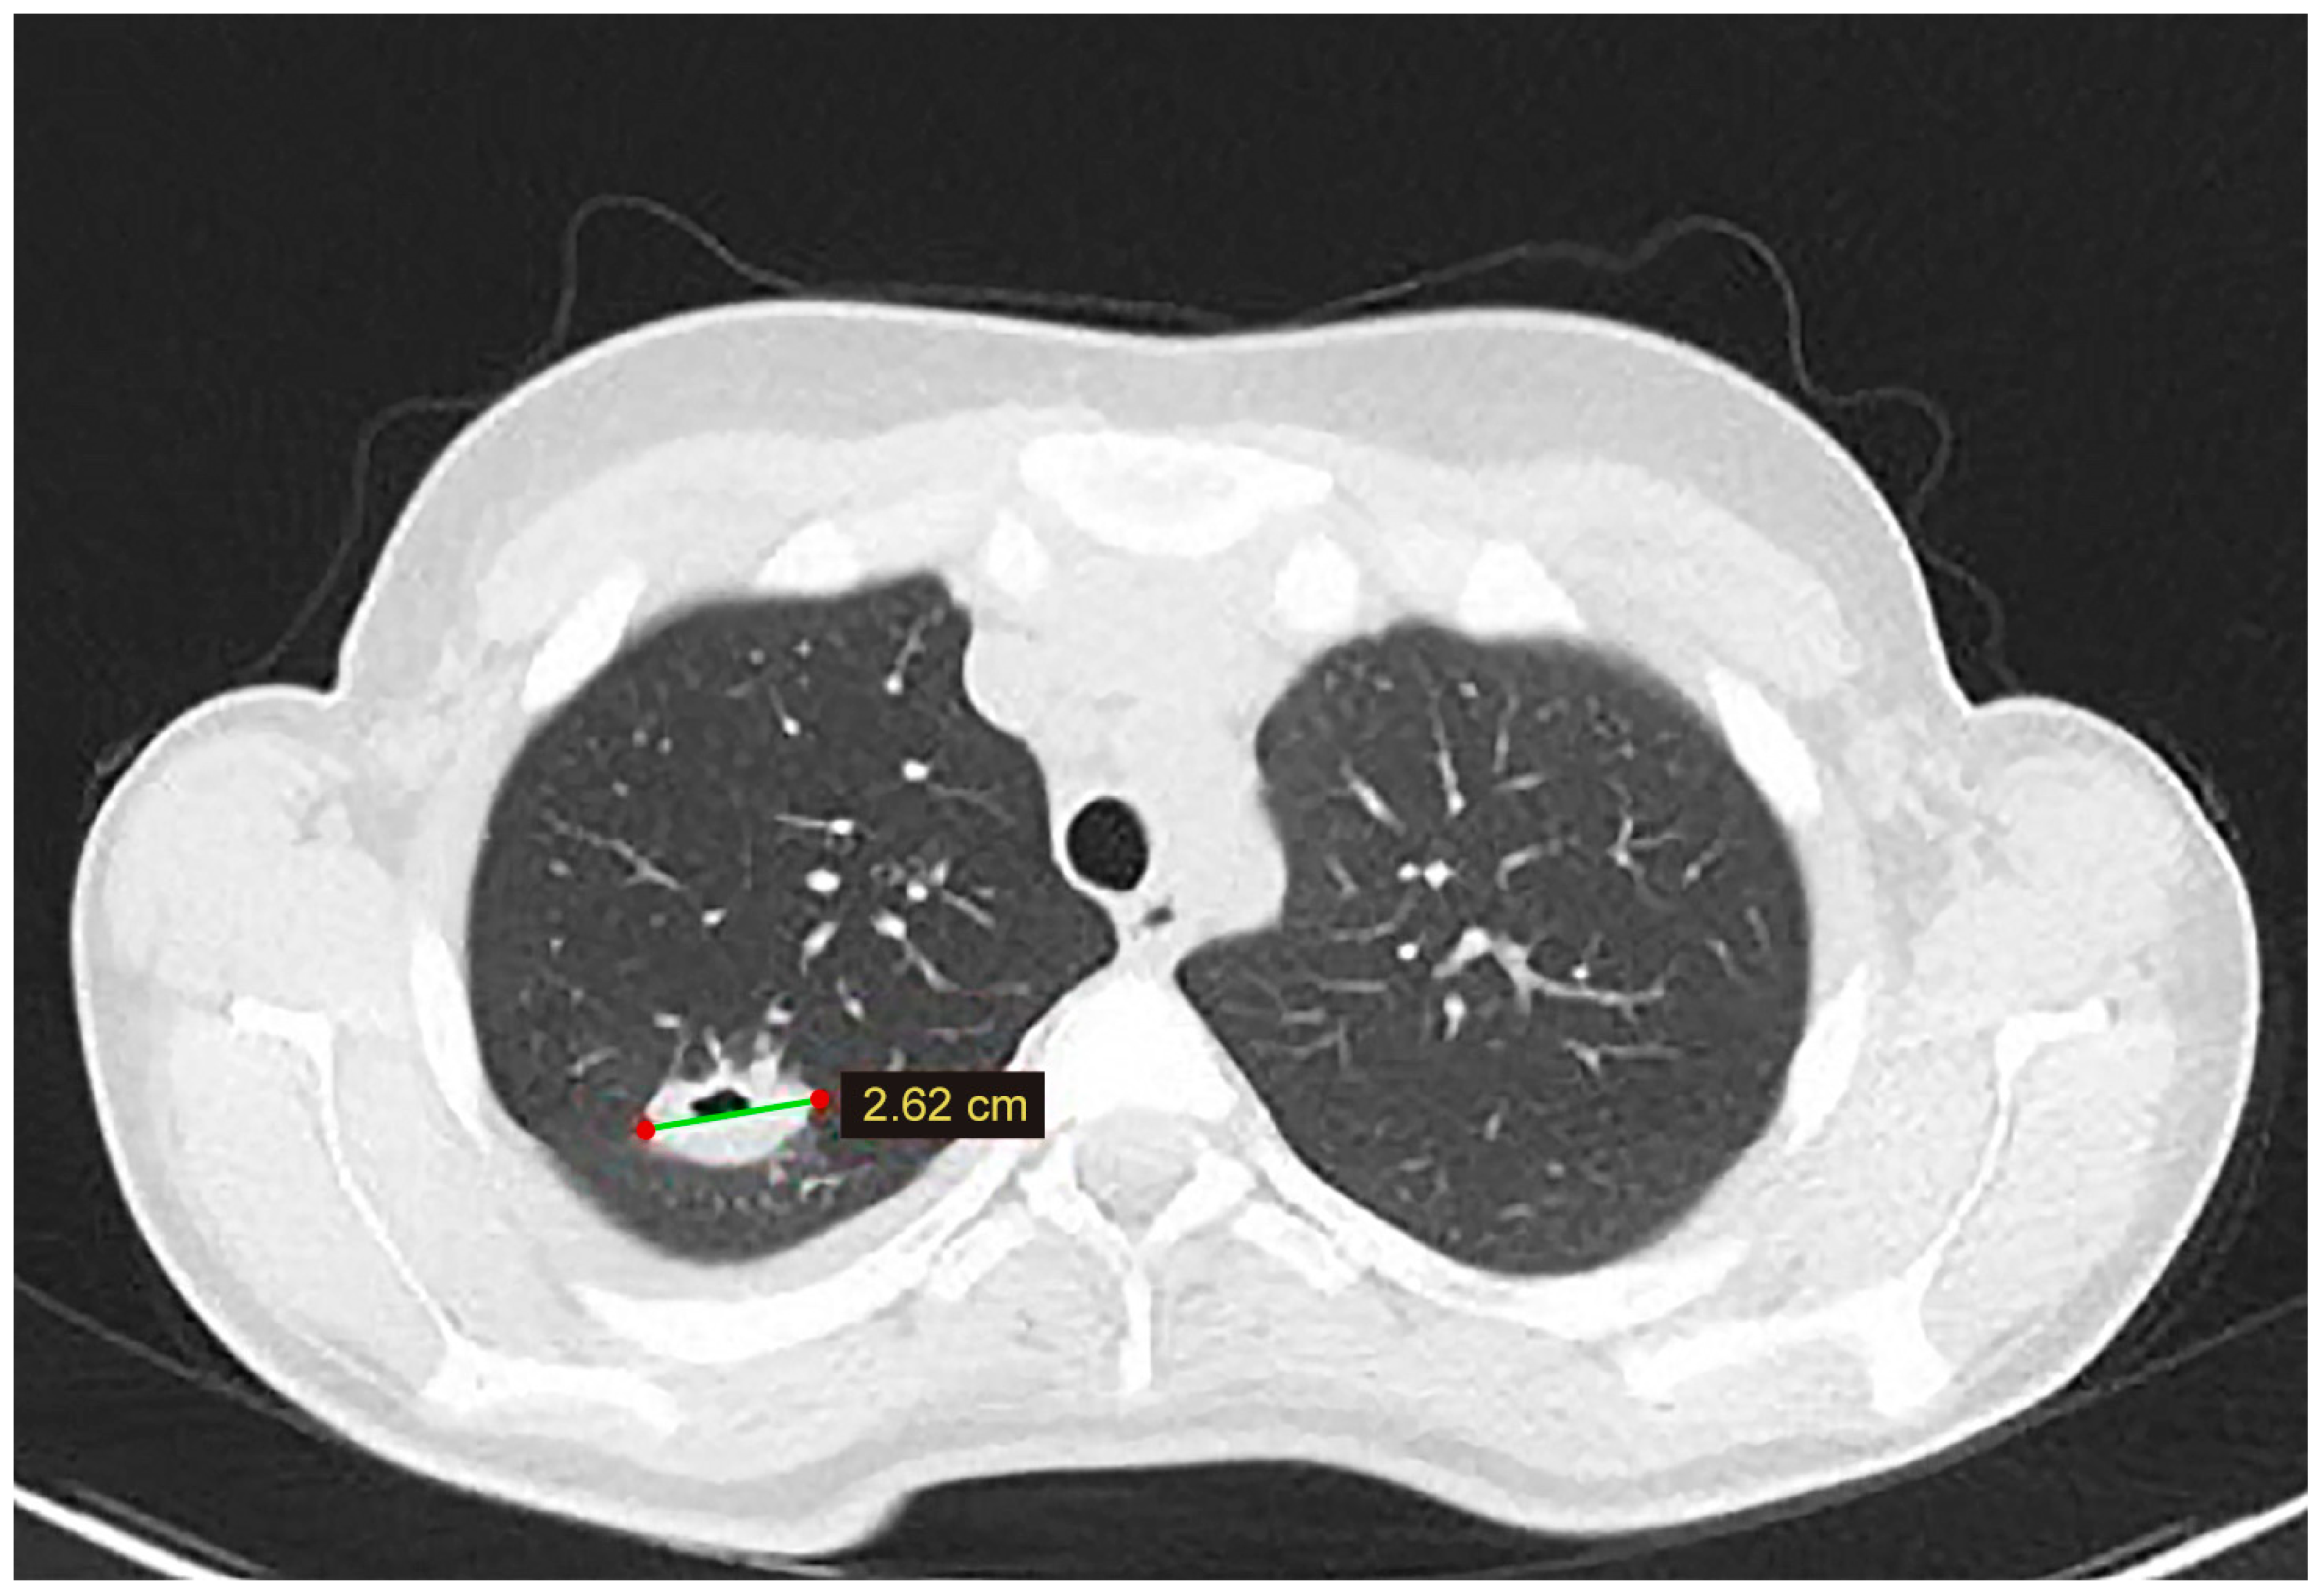

3.1. Case 1